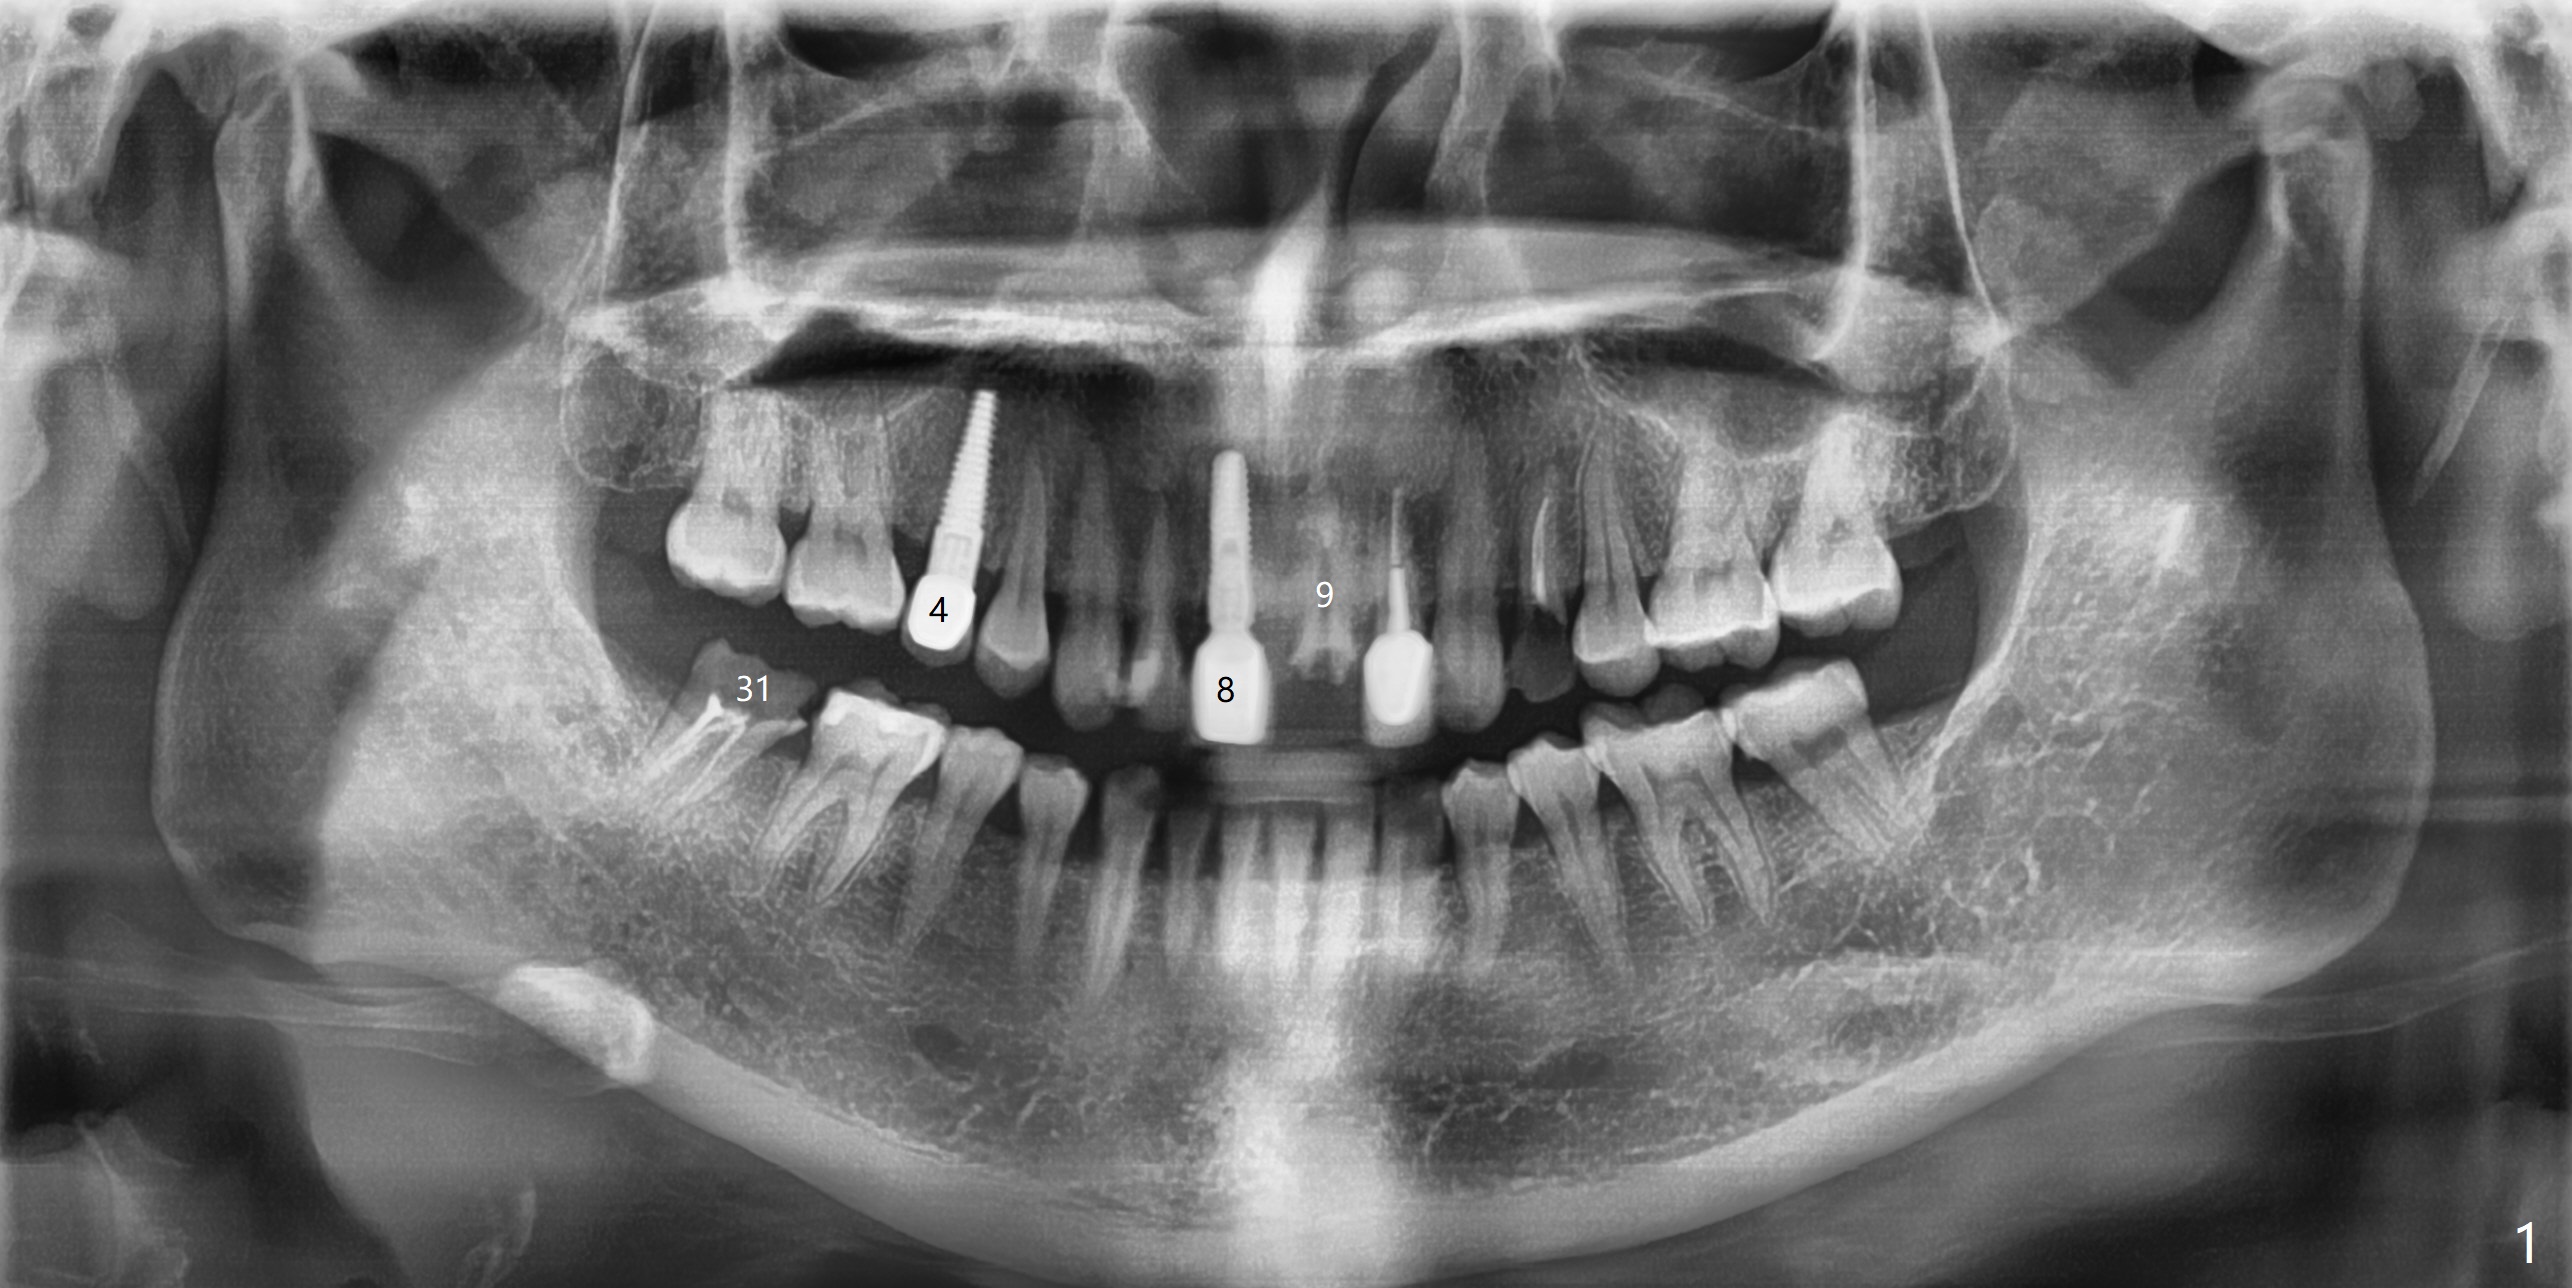

A 43-year-old woman will return for #9 and 31 implant placement. To prevent periimplantitis, a smaller implant will be placed deeper at #9 (3.8 or 4.1x14 mm) vs. 4.5x14 mm at #8 (2 years post cementation). The same type of implant (easy cement removal vs. the one at #4 (4.5x17 mm; 2 years post cementation)) will be placed at #31 mesial socket (Fig.2-4: 4.5x8.5 or 10 mm, never pass beyond the distal apex of the tooth #30: *). In fact, the tooth #9 is salvageable. Finally the patient decides to work on the tooth #12 (the same implant as #4). Take photos to show the residual roots. If there is buccal plate atrophy, prepare for socket shield.